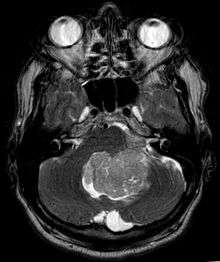

Ependymoma is a tumor that arises from the ependyma, a tissue of the central nervous system. Usually, in pediatric cases the location is intracranial, while in adults it is spinal. The common location of intracranial ependymoma is the fourth ventricle. Rarely, ependymoma can occur in the pelvic cavity.

Ependymomas make up about 5% of adult intracranial gliomas and up to 10% of childhood tumors of the central nervous system (CNS). Their occurrence seems to peak at age 5 years and then again at age 35. They develop from cells that line both the hollow cavities of the brain and the canal containing the spinal cord, but they usually arise from the floor of the fourth ventricle, situated in the lower back portion of the brain, where they may produce headache, nausea and vomiting by obstructing the flow of cerebrospinal fluid. This obstruction may also cause hydrocephalus. They may also arise in the spinal cord, conus medularis and supratentorial locations.[4] Other symptoms can include (but are not limited to): loss of appetite, difficulty sleeping, temporary inability to distinguish colors, uncontrollable twitching, seeing vertical or horizontal lines when in bright light, and temporary memory loss. It should be remembered that these symptoms also are prevalent in many other illnesses not associated with ependymoma.